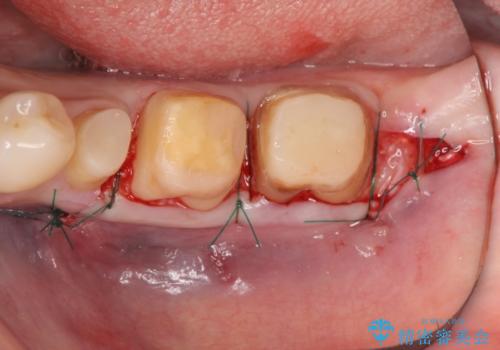

- 左下の歯が虫歯により崩壊し、歯ぐきからの出血も毎回歯ブラシを行う際に出ることから治療を求めて来院されました。

現在装着されているクラウンを除去したところ、クラウンマージンが歯肉縁下となり歯ぐきの炎症が認められたため再度オールセラミッククラウンを製作する前に歯周外科手術を行い歯ぐきの状態を改善しました。